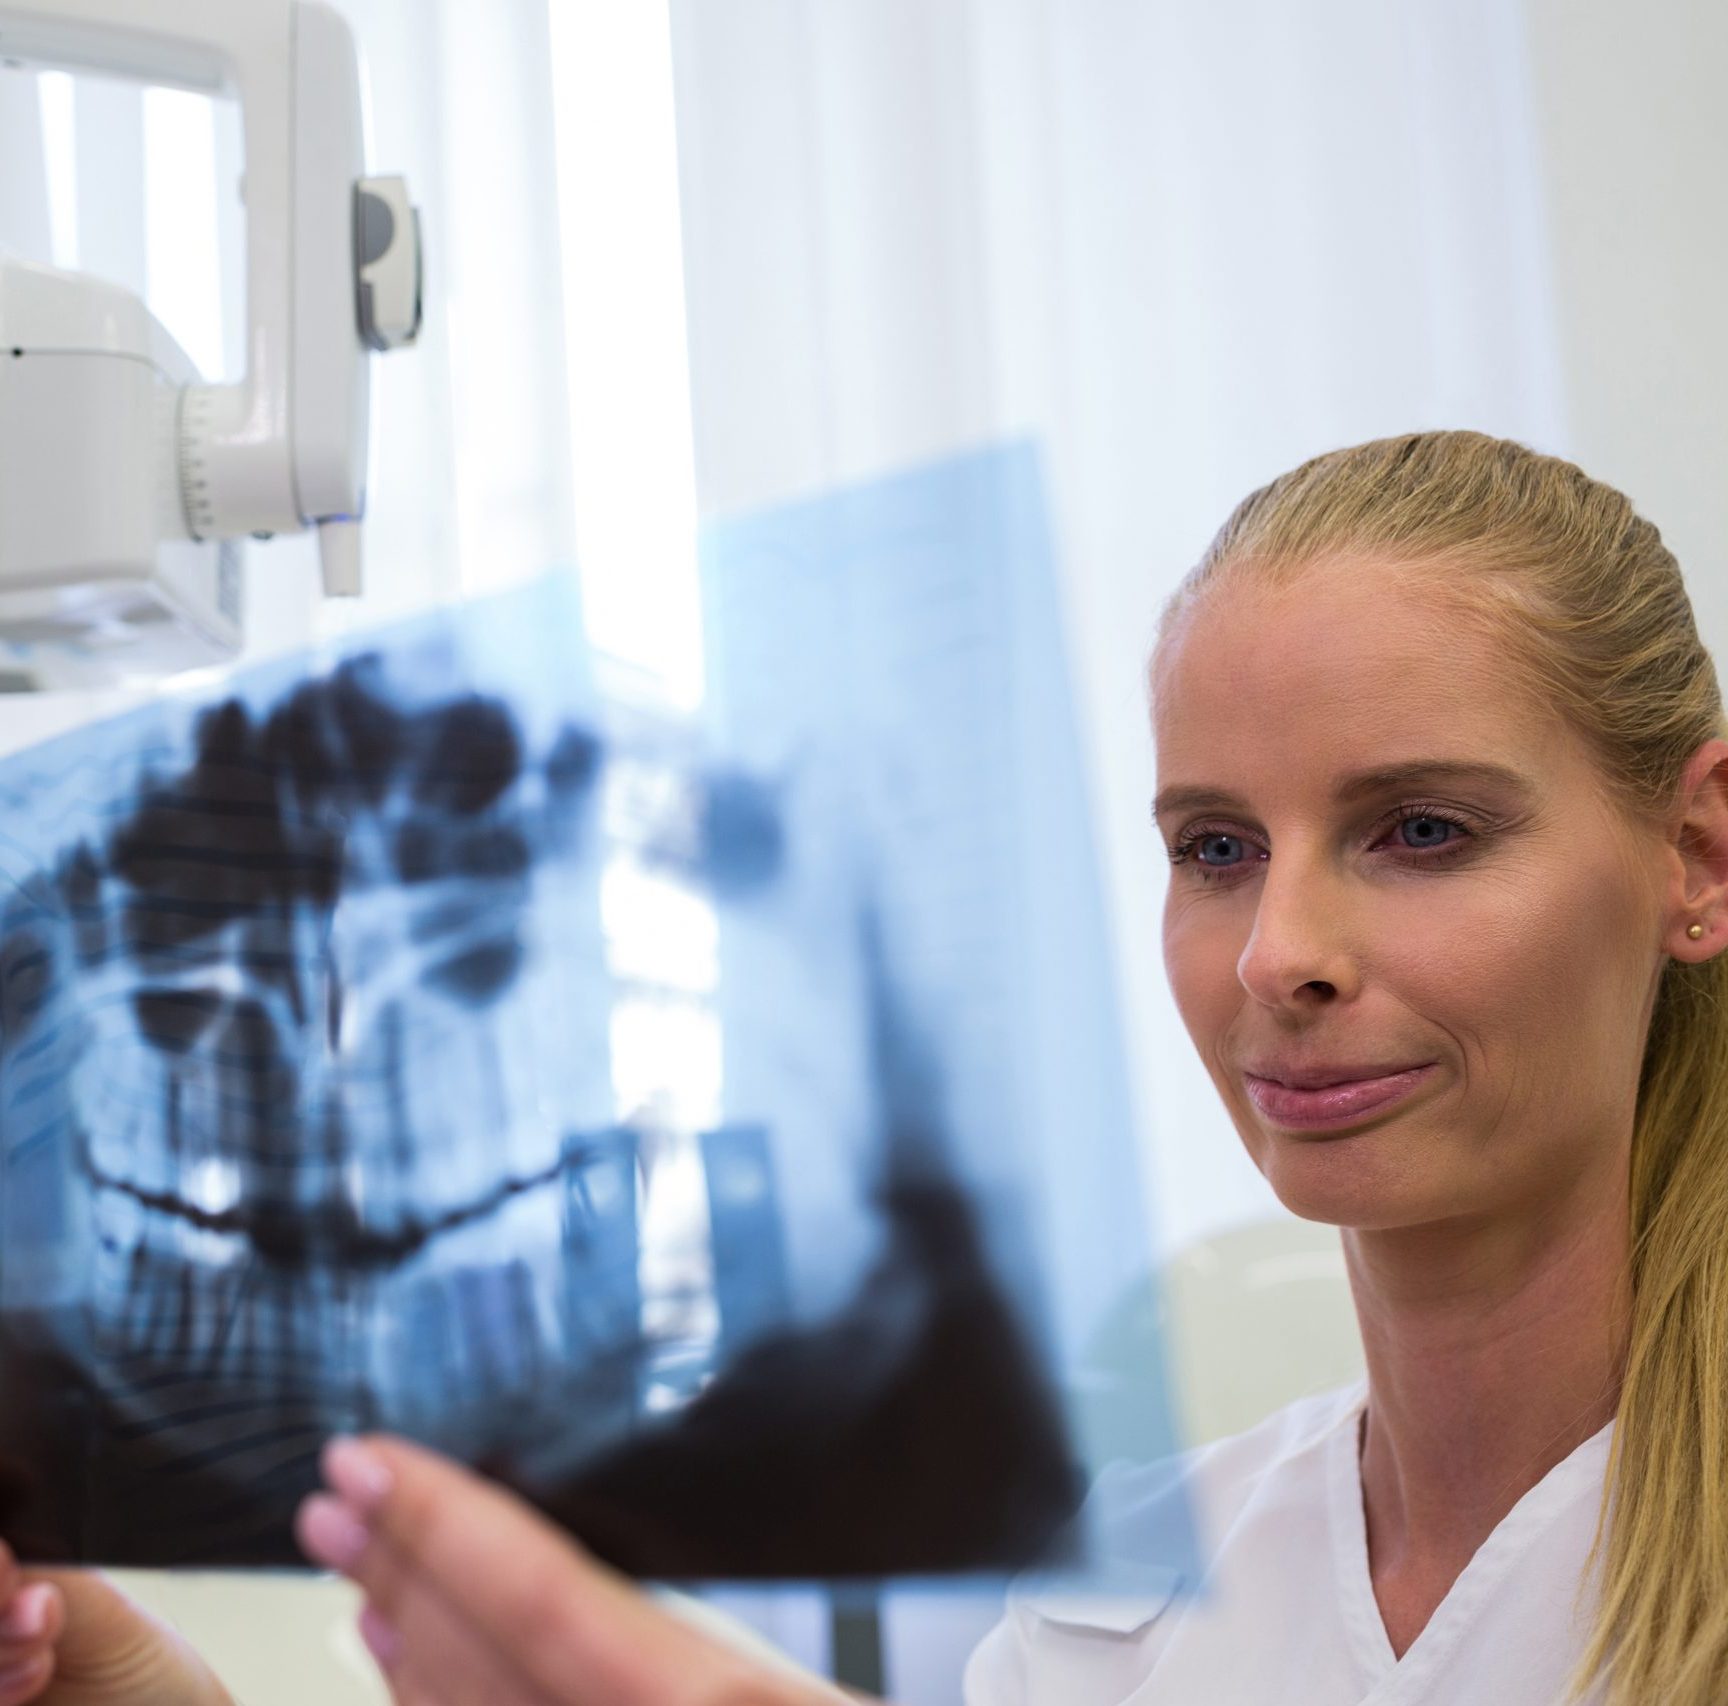

Radiografii gratuite prin C.A.S

La Dabrident Clinic by Dr. Ciuntea, te așteptăm cu radiografii dentare digitale GRATUITE prin C.A.S.! Beneficiezi de cea mai bună calitate cu radiații minime pentru un diagnostic precis. Doar în clinica George Bacovia!

Radiografii gratuite prin C.A.S

La Dabrident Clinic by Dr. Ciuntea, te așteptăm cu radiografii dentare digitale GRATUITE prin C.A.S.! Beneficiezi de cea mai bună calitate cu radiații minime pentru un diagnostic precis. Doar în clinica George Bacovia!